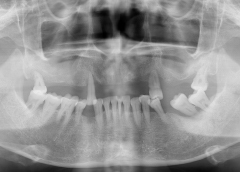

• Tình trạng răng trước đây:Mất nhiều răng lâu năm, tiêu xương hàm.

• Bác sĩ chỉ định:Cấy ghép 6 trụ Implant.

• Implant sử dụng: Implant Straumann Thụy Sỹ

Cô Hồng Phương được chỉ định cấy ghép 6 trụ Implant Straumann SLActive Thụy Sỹ, loại trụ cao cấp nhất thế giới hiện nay. Nhờ đó rút ngắn được thời gian phục hình sứ và giúp cô sớm có được hàm răng mới ăn nhai cứng chắc.